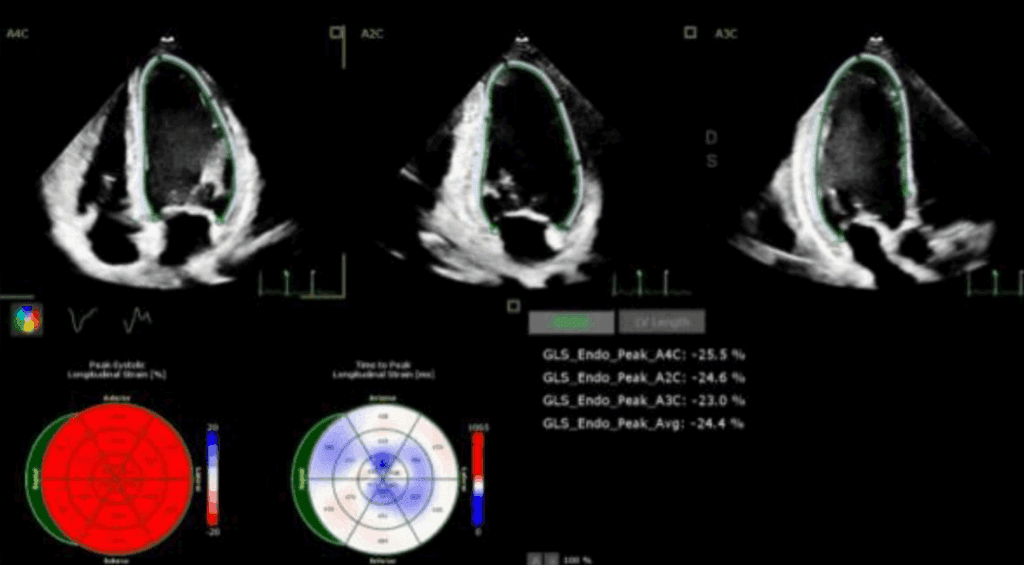

Odkształcenie mięśnia sercowego (strain) jest metodą diagnostyczną oraz coraz lepiej udokumentowanym parametrem prognostycznym, który uzupełnia standardowe przezklatkowe badanie echokardiograficzne (ang. transthoracic echocardiography – TTE).